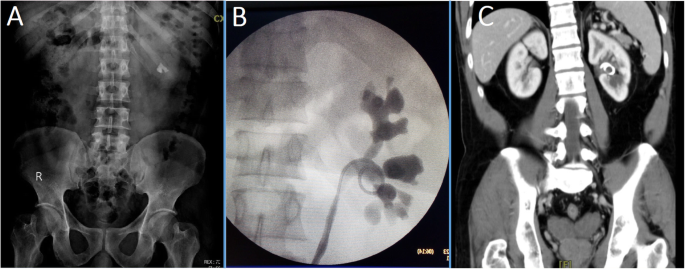

A 32 years old female presented with right flank pain and a history of urinary tract infections. Imaging revealed a large right staghorn stone (Fig. 2a). So, she underwent prone PNL using Amplatz dilators. Three ports were used and similar to the first patient, there was a perforation of the renal pelvis by the tip of the sheath. The perforation was large and in view of the excessive bleeding and the fear of significant extravasation, the procedure was stopped before total clearance of the stone. The collecting system was then drained by two nephrostomy tubes and antegrade placement of a JJ stent (Fig. 2b). Post-operatively, she did well, and the two drains were removed on the second post-operative day. In view of the remaining fragments, she opted to undergo fURS and laser lithotripsy 6 weeks following the PNL. However, trial to remove the JJ stent failed and the stent was found to be embedded in the renal tissues as shown by the retrograde pyelography (Fig. 2c). Therefore, using a rigid ureteroscope, the stent was transected at the junction of the upper coil with the stem and a trial to perform a fURS failed due the inability to pass an access sheath (12/14Fr). So another stent was placed (Fig. 2d) until 8 weeks later when she was consented for PNL but she asked if she could have one more trial of fURS in the same sitting. By that time, and by using a smaller access sheath (10/12Fr which was not available in the first session), fURS was performed and the JJ stent upper coil was released by laser incision of the tissues trapping the stent coil. The stent coil was removed completely. At the same session, she underwent laser lithotripsy of the remaining stones and the procedure was uneventful with smooth post-operative recovery.

Imaging of the second case. a, Pre-operative plain x-ray with full staghorn calculus; b, Immediate post-operative plain x-ray showing the two nephrostomy drainage tubes clamped and the JJ stent in position with the remnant stone fragments; c, Retrograde pyelography showing the loop of the JJ stent outside the collecting system; d, Plain x-ray showing isolated upper coil of the embedded stent following transection of the stent at the junction of the coil with the stem using rigid ureteroscopy. Another JJ stent was placed during the procedure